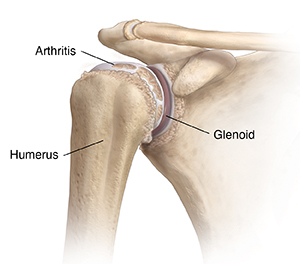

A joint is where 2 or more bones meet. The glenohumeral joint is the main joint in the shoulder. It is a ball-and-socket joint. It is formed where the head or ball of the upper arm bone fits into the shallow socket on the shoulder blade. The upper arm bone is called the humerus. The socket is called the glenoid. This is how the joint gets its name. When the glenohumeral joint is healthy, it helps you rotate and move your arm freely without any pain.

All joints contain a smooth tissue called cartilage. Cartilage cushions the ends of bones. This helps them glide smoothly against each other. Glenohumeral osteoarthritis occurs when cartilage in the glenohumeral joint starts to break down. The ball and socket bones may then become exposed and rub together. The bones may become rough and pitted. They may start to wear away. This prevents smooth movement of the joint.